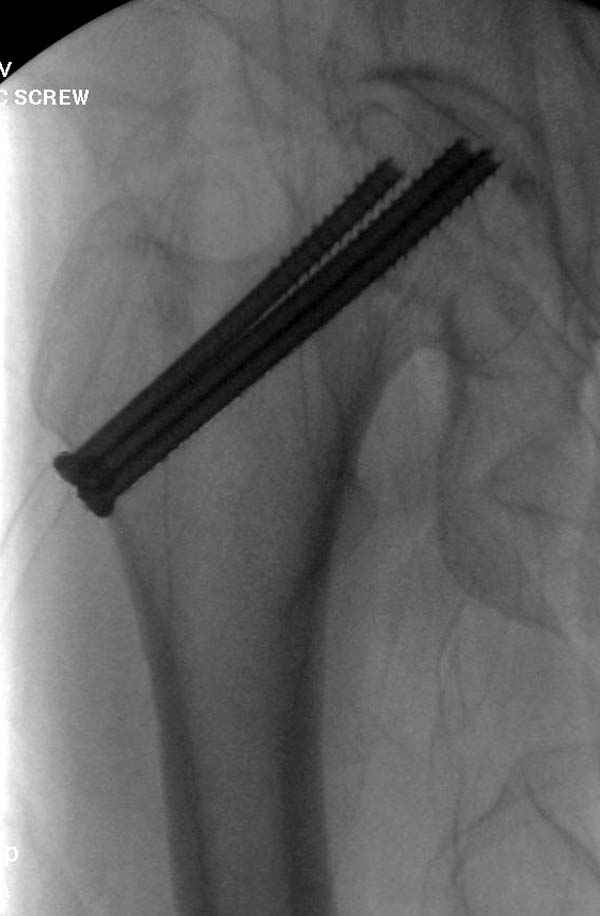

На второй день после выписки упал дома. Снимки приложены. Коллеги рекомендуют удаление шурупа и вытяжение. Что делать?

Правильно, ситуация изменилась, как говорят у нас теперь "different animal", надо решать проблему подвертельного перелома. При наличии различных вариантов фиксаторов, включая Страйкер Гамма 3, мы выбрали DePuy Antegrade Trachanteric Nail из-за многовариантности проксимальной фиксации и двойного изгиба. Вводится через вертел под 8 градусным углом, и есть достаточный передний диафизарный изгиб, предупреждающий пенетрацию дистального переднего кортекса.